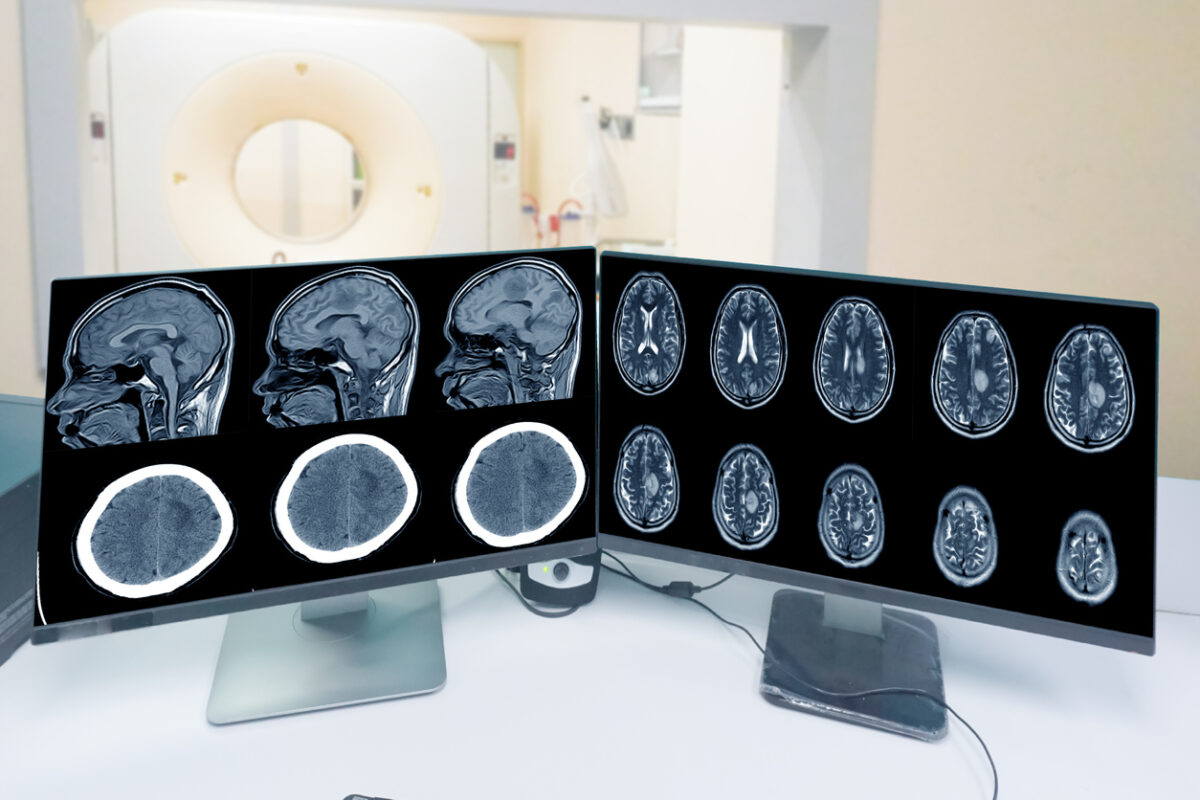

Close up CT-scan control room and showing brain image meningioma in brain CT scan room background, Medical healthcare, and technology concept.